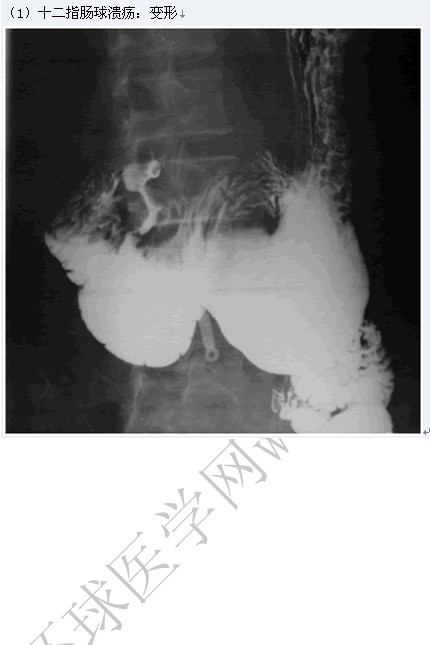

十二指肠造影